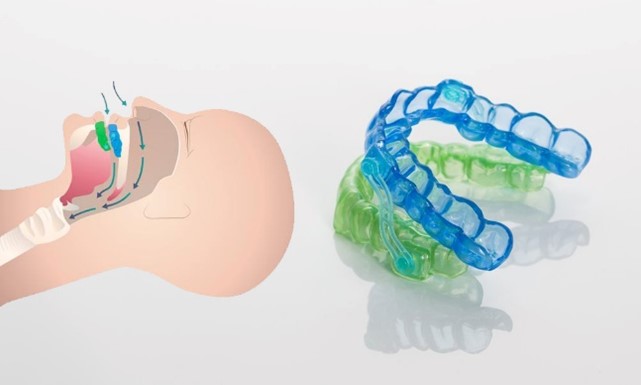

Silensor se sastoji od jedne zubne udlage za gornju čeljust i jedne zubne udlage za donju čeljust. Donja čeljust se zadržava u prednjem položaju (protruzija) s dvije spojnice koje su fiksirane bočno na udlagama. Na taj način silensor sprječava približavanje stijenki mekih tkiva. Sa silensor udlagom pokreti donje čeljusti su mogući lijevo-desno i naprijed bez povlačenja unatrag.

Zbog ove funkcije silensor je istodobno učinkovit i udoban. Klinički testovi su pokazali da potiskivanje donje čeljusti prema naprijed značajno smanjuje hrkanje za kod više od 90% pacijenata i može smanjiti indeks apneje za 50%